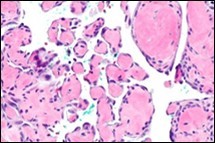

On microscopy, superficial squamous epithelial surface is intact. Sub-epithelial connective tissue stroma exhibits slit-like, vascular spaces. Upon extended magnification, multiple, intravascular papillary projections encompassed within a hyalinised stroma are discerned. Centroidal calcification appears in combination with intravascular, papillary endothelial cell proliferation, lined with singular layer of endothelial cells devoid of cytological atypia6, 7.

Characteristically, the vascular neoplasm denominates numerous papillae within blood vessels. Papillae are coated with singular or dual layer of flattened endothelial cells with an encompassing hyalinised, fibrous tissue core. Vascular lumen is distended with thrombosis. Foci of haemorrhage with fibrinous and purulent exudate are discerned. Tumour perimeter depicts inflammatory granulation tissue. Cholesterol clefts and focal reactive bone formation may concur. Extraneous squamous epithelium may be discontinuous and ulcerated. The neoplasm is devoid of features of malignancy4, 6.

Numerous micro-calcifications can be observed within the lesion which may engender vascular occlusion and tissue necrosis6. Figure 1, Figure 2, Figure 3, Figure 4, Figure 5, Figure 6, Figure 7, Figure 8.

Figure 2 Papillary endothelial hyperplasia delineating papillary articulations with an endothelial cell layer, thrombotic exudate and fibrinous debri (1.